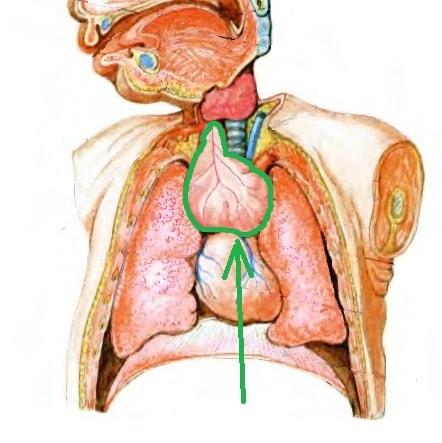

Тимомегалия: что это такое и как проявляется